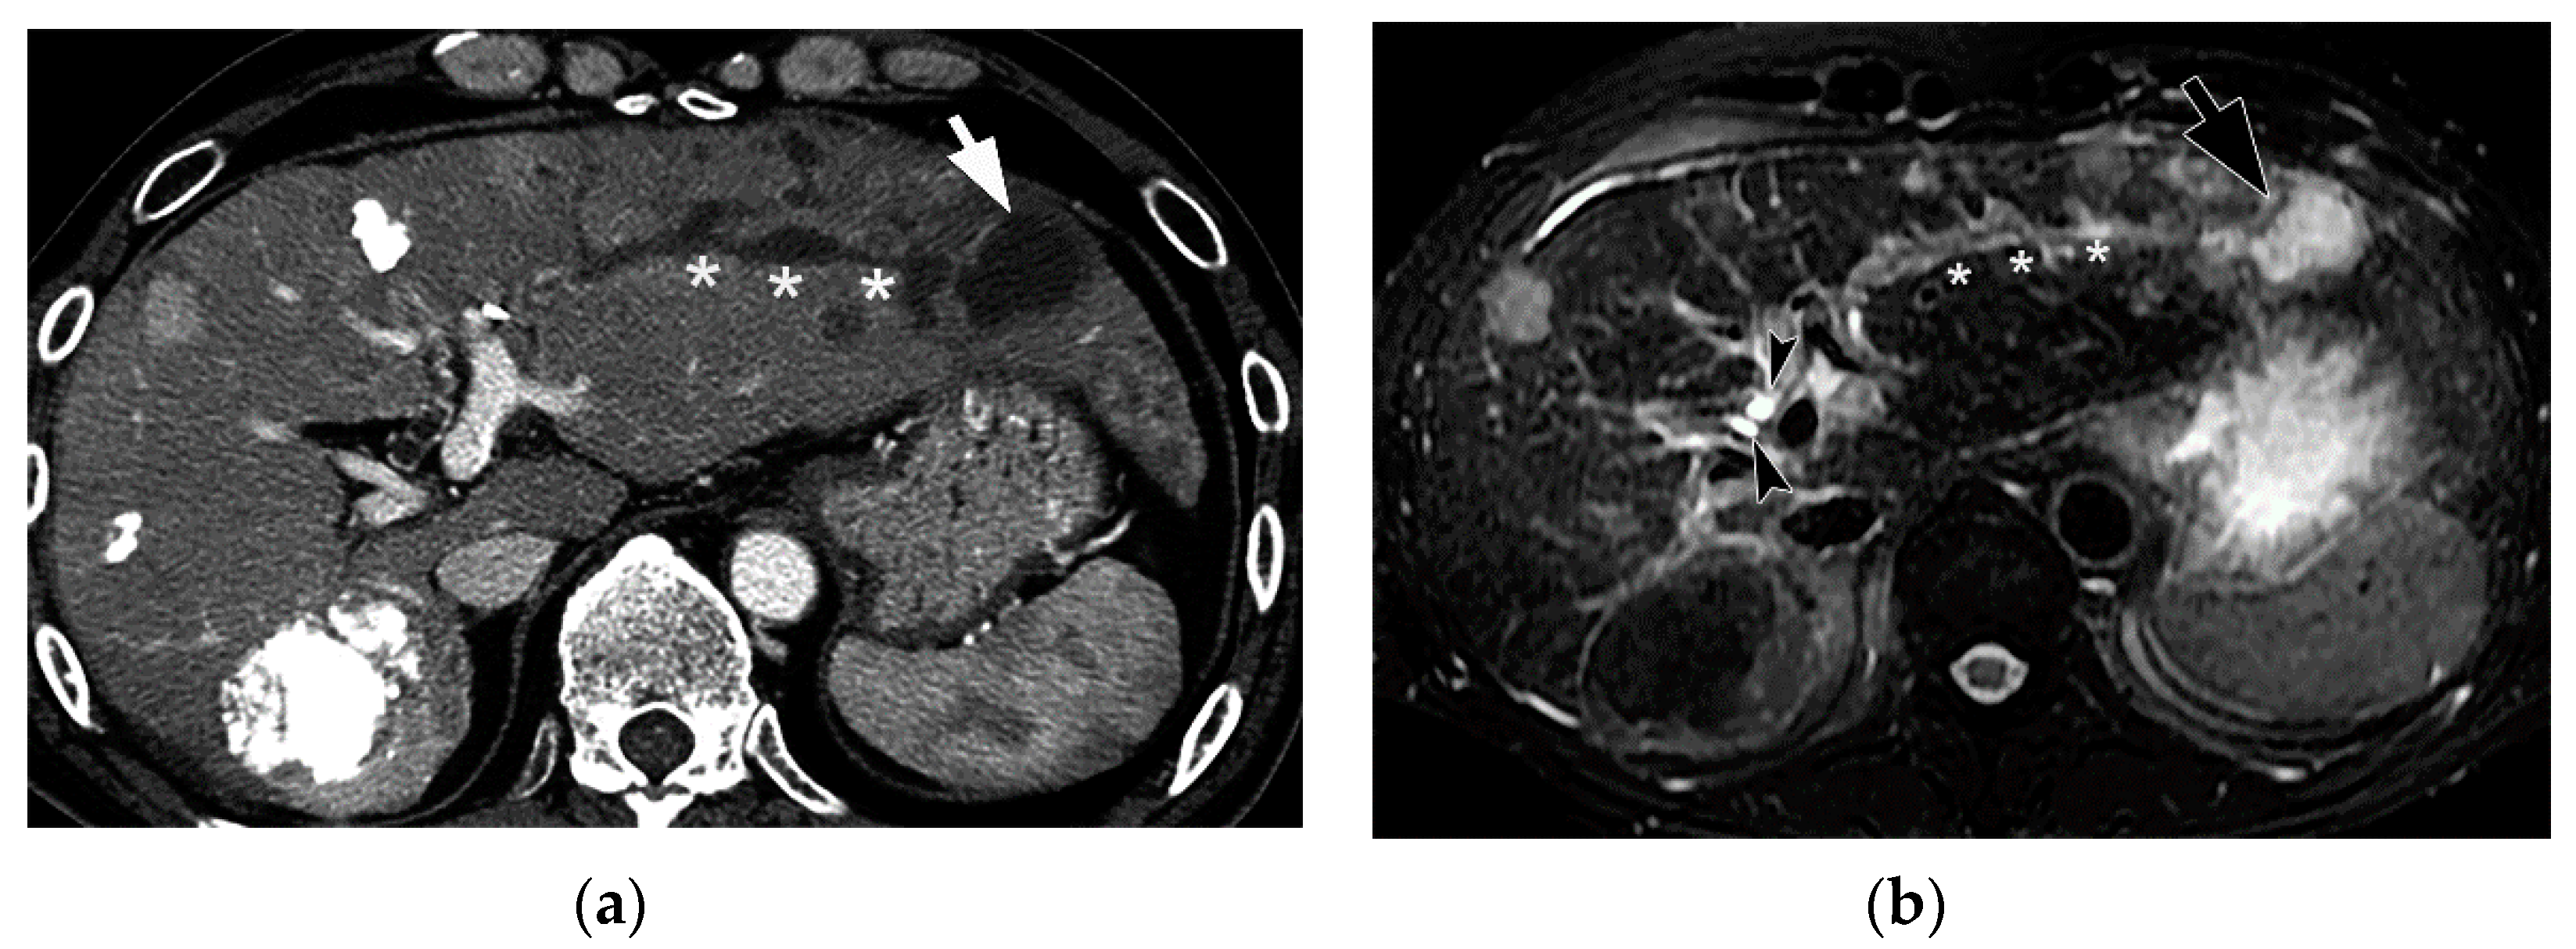

Figure 12. Comparison between CT and ultrasound (US) findings of BDN. (a) On contrast-enhanced CT, a hypodense thick tubular structure (arrow) is observed in the hepatic hilum of the right hepatic lobe, and in the left lateral segment, a similar hypodense thin tubular structure (arrowheads) is observed. Although these tubular hypodense structures look like dilated intrahepatic bile ducts, the right lobe lesion is BDN and the left lateral lobe lesion is bile duct dilatation. (b) On US images of the right hepatic lobe, no dilated bile ducts are observed in the portal tract. The portal tract shows iso- to slightly hyper-echo compared to the surrounding liver parenchyma (arrows). This US finding is inconsistent with the CT finding. (c) In the US image of left lateral lobe of the liver, a slightly dilated echo-free tubular structure (arrows) is observed along the arterial branch, which represents intrahepatic bile duct dilatation. As indicated on Figure 12b, BDN is iso- to slightly hyper-echo compared to the surrounding liver parenchyma and shows discrepancy with the CT finding.